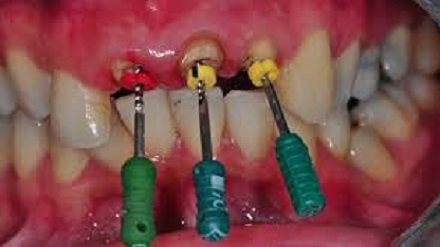

Root Canal

Root canal treatment consists of a number of steps that take place over several office visits, depending on the situation. These steps are: The endodontist examines and x-rays the tooth, then local anesthesia is administered to the affected tooth. A dental dam is usually placed over the affected tooth to isolate it and keep it free from saliva. The endodontist makes an opening through the back of a front tooth or the crown of a molar or pre-molar to remove the diseased pulp, called a pulpectomy. Next, the pulp chamber and root canals are cleaned and shaped in preparation for a filling. The endodontist fills the root canal with gutta percha material. If more than one visit is needed, a temporary filling is placed in the crown opening to protect the tooth between dental visits. The temporary filling is removed and the pulp chamber and root canal are permanently filled with gutta percha into each of the canals and is sealed in place with cement. Sometimes a metal or plastic rod is placed in the canal for structural support. In the final step, a crown is usually placed over the tooth to restore its natural shape and appearance. If the tooth is broken, a post may be required to build it up prior to placing a crown.